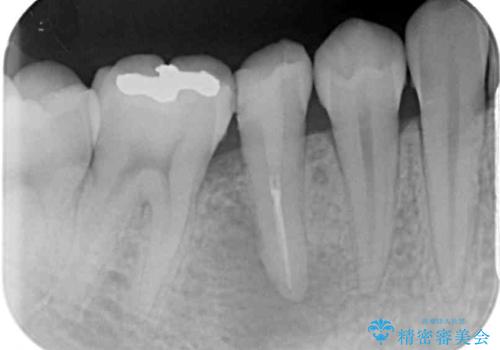

以前通われて医院にて、再度根管治療が必要であると伝えられていたようですが、レントゲン写真などの診察を行った結果、再根管治療が必要な状態でした。

レントゲン写真より、当該歯周囲に大きな透過像があり、歯槽骨が炎症により吸収している様子が認められます。

根管治療後9ヶ月で撮影したレントゲン写真より、歯根周辺の透過像が十分に消失している様子が認められました。